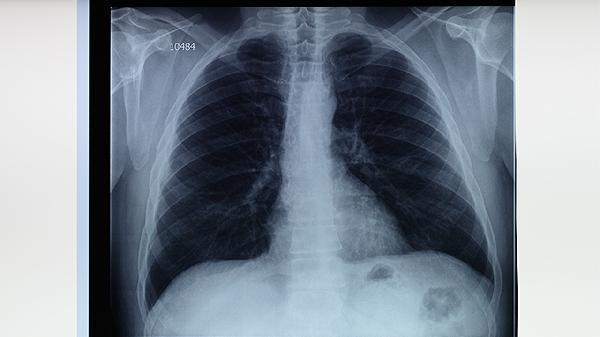

治疗初期每2周复查血常规和肝肾功能,稳定后每月1次。痰涂片检查需持续3次阴性才可判定无传染性。胸部X线或CT随访建议每3个月1次,观察病灶吸收情况。若出现咯血、持续发热需立即复诊。